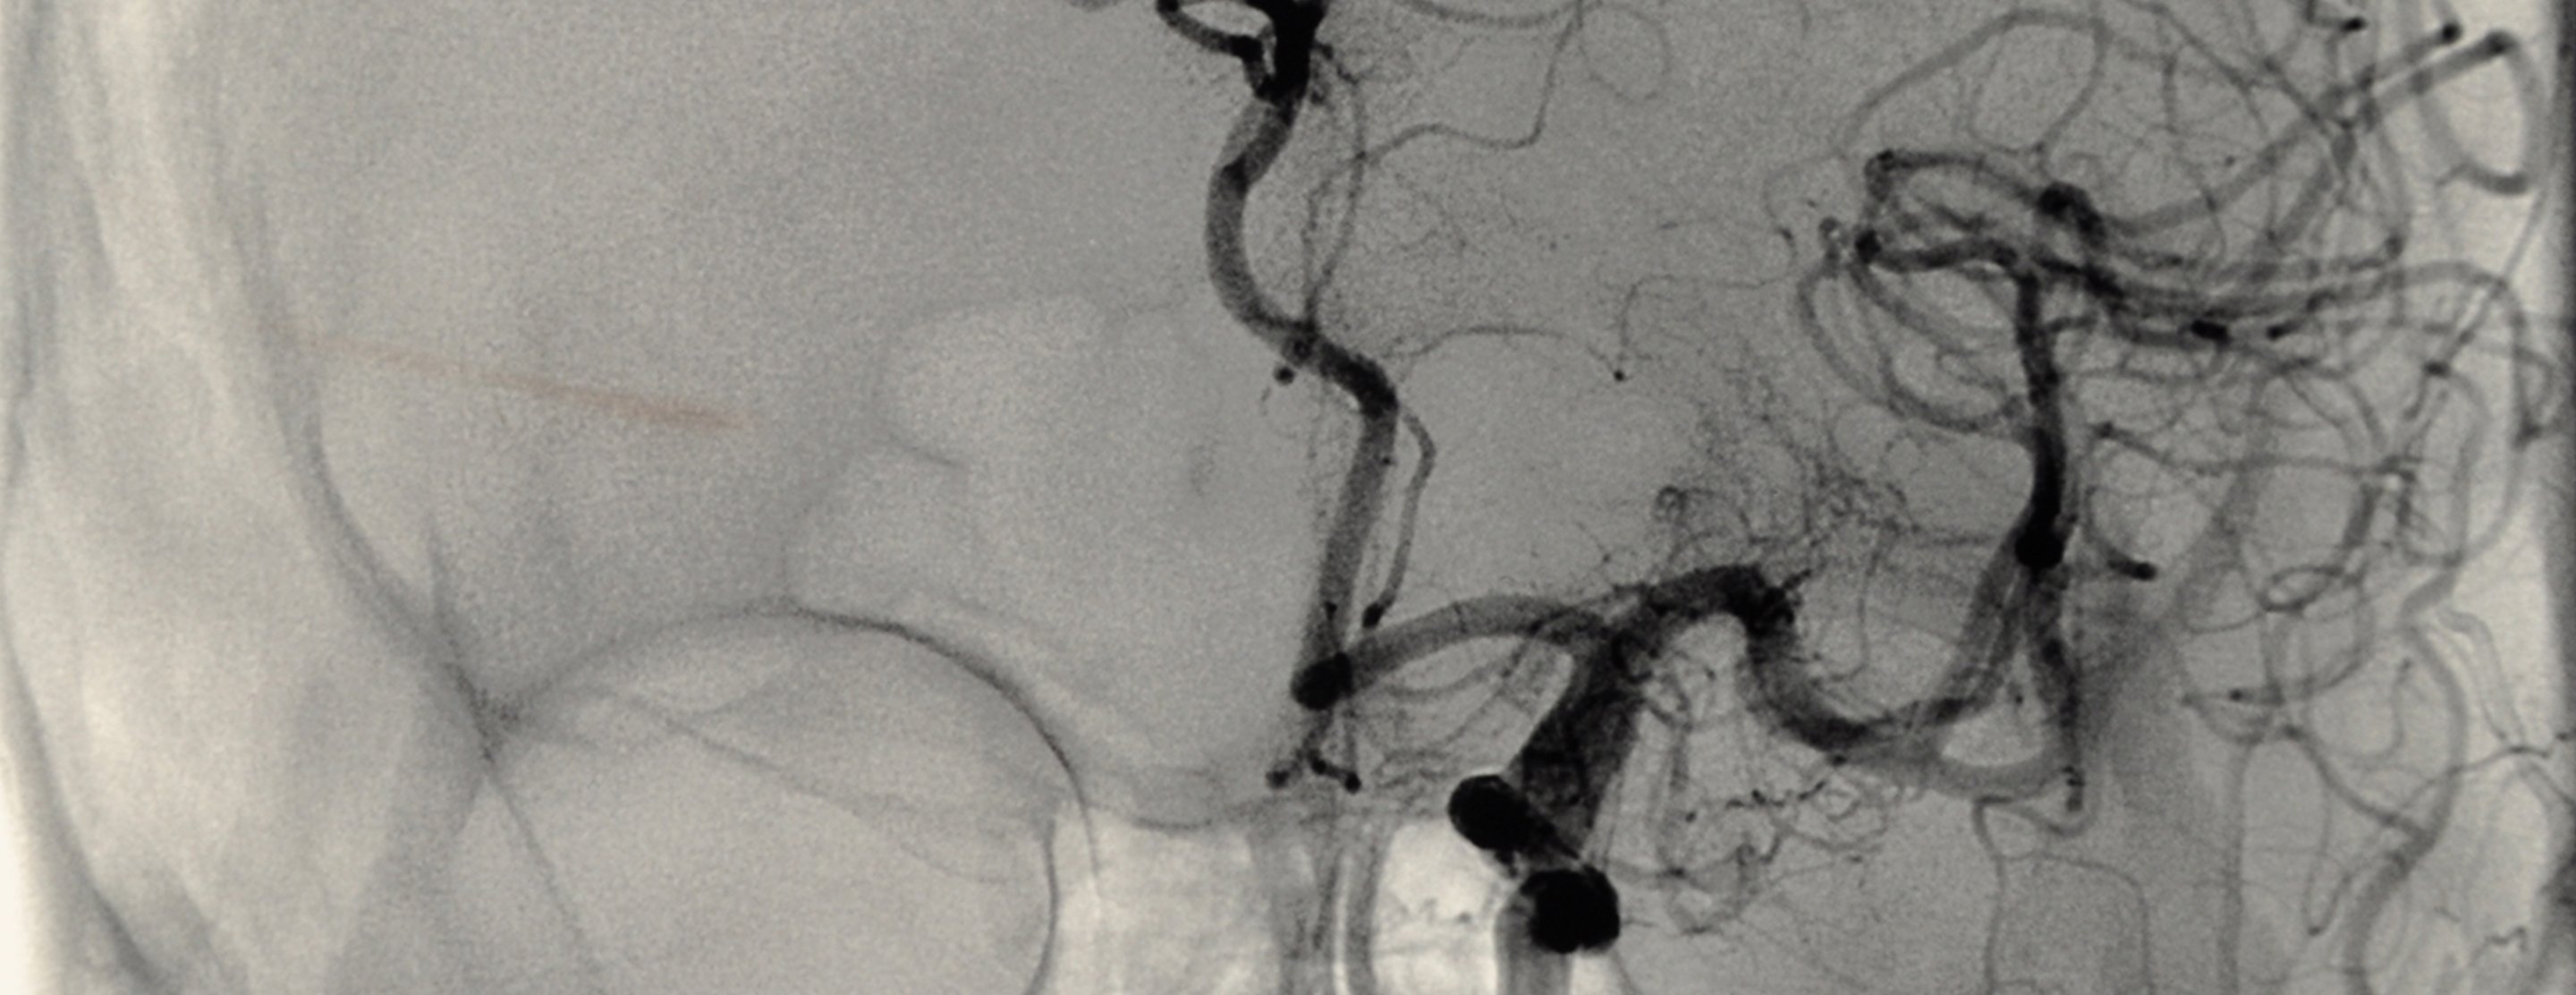

Cerebral angiography is a procedure that uses a special dye (contrast material) and x-rays to see how blood flows through the brain.

Once the catheter is in place, dye is sent through the catheter. X-ray images are taken to see how the dye moves through the artery and blood vessels of the brain. The dye helps highlight any blockages in blood flow.

Sometimes, a computer removes the bones and tissues on the images being viewed, so that only the blood vessels filled with the dye are seen. This is called digital subtraction angiography (DSA).